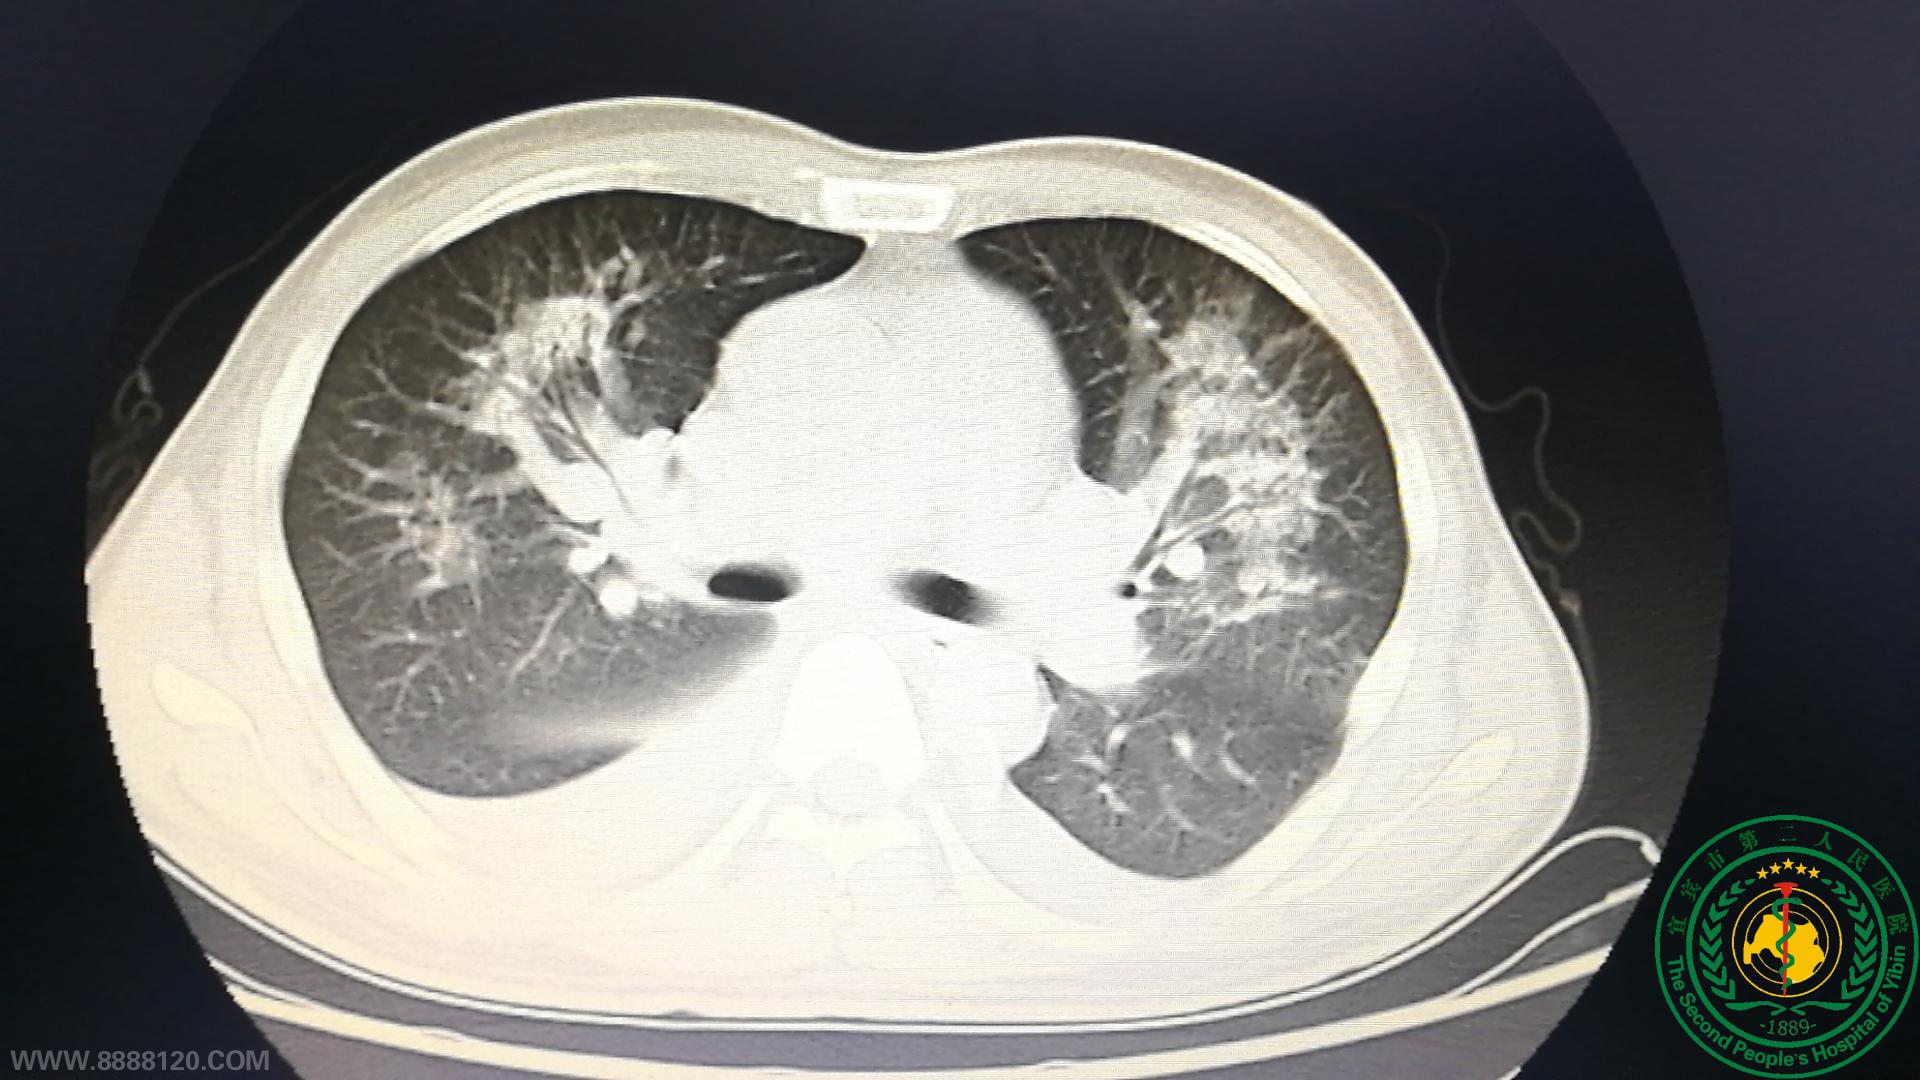

2020.11.23日胸心外科杨朝坤主任医师带领心外科团队在麻醉科、手术室的密切协作下为患者实施了体外循环下主动脉置换+二尖瓣穿孔修补成形+三尖瓣成形+房间隔缺损修补+室间隔缺损修补术,经历手术6小时,术后患者入胸心外科监护室监护治疗。但因患者术前肺部感染重,又有手术打击,术后即使呼吸机支持机体氧供仍然极差,主管医生刘德胜(华中科技大学同济医学院心脏外科硕士研究生)和护理人员术后寸步不离坚持守候患者床旁密切监护患者病情变化,及时认真分析精准处置患者呼吸循环的各种变化及术后并发症,历时48小时的努力付出和精心监护,患者顺利撤离呼吸机转回普通病房继续监护,经过医护人员长时间的精心救治,患者层层闯关最终康复出院。